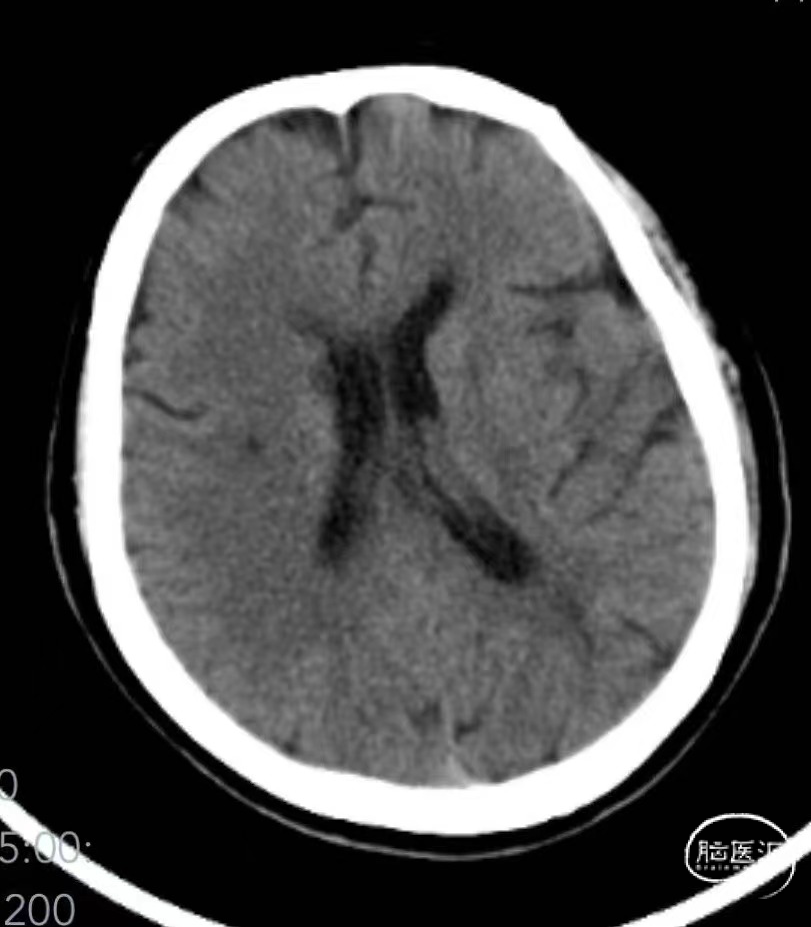

➤2024.3.20 头颅MRI

左侧基底节区/侧脑室旁及额顶枕叶急性期脑梗死。